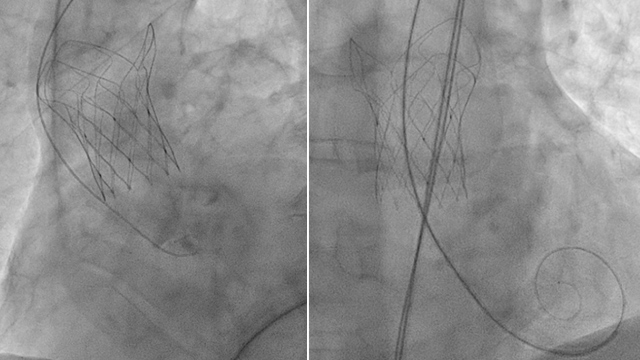

Rapid-Fire - TAVI complications: valve embolization, balloon ruptures & more!

Dive into this rapid-fire session showcasing a collection of captivating TAVI complication cases from PCR London Valves 2024. Witness the highs and lows of TAVI procedures, from valve embolization and parallel wiring to balloon ruptures and deformed valves. Gain valuable insights through reflective learning and discover...